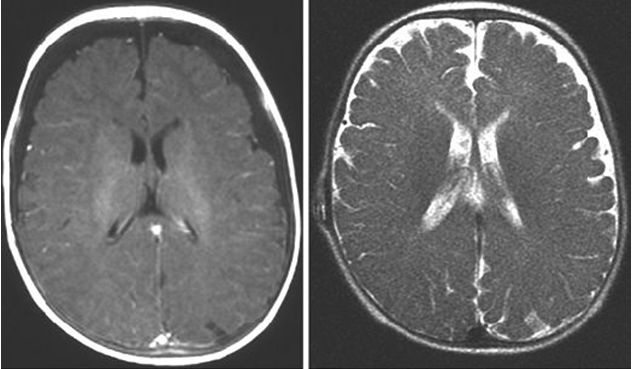

El diagnostico lo da la ecografía transfontanelar, la Tomografía computarizada, se reserva para aquellos que muestren una ecografía anormal. En manos de un ecografista entrenado, las imágenes de la ecografía son muy sugestivas del diagnostico de HEI, y no se requiere mayores estudios en niños por otro lado normales. La HEI es una entidad benigna y autolimitada, relativamente frecuente en pediatría.

Descripción de la ecografía: una colección de líquido interhemisférico de 5,5 mm que se extiende a la convexidad (5,5 mm a la izquierda y 6 mm a la derecha) sin compromiso del sistema ventricular - fue comun a todos los pacientes, variando las mediciones.

TAC, de HEI.